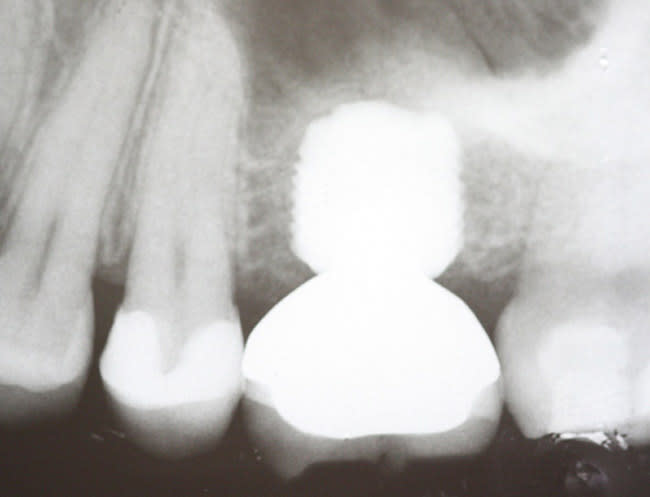

The MegaGen Rescue is a parallel-walled implant with threads to the crest of the implant. It has a resorbable blast medium (RBM) hydroxylapatite treated surface. The thread pitch (0.8 mm) is narrowed to compensate for its reduced dimension; heights range from 5 mm to 11.5 mm and diameters range from 6 mm to 8 mm. It is designed to engage the walls of the edentulous socket for primary stability. The prosthetic design is platform-switched. The neck of the abutment is 4 mm in diameter, and the screw is quite robust, with a diameter of 2.5 mm. The torque value for tightening the screw is 45 Ncm.

Four months after placement, the healing abutment was removed and a closed-tray impression obtained. A screw-retained metal ceramic crown using a 50% gold alloy was made, evaluated intraorally in the bisque stage, contoured, and the occlusion adjusted. After glazing and polishing, the crown was inserted.

Radiographs using a standardized holder were taken at the time of implant insertion, at the time of crown insertion, 6 months after crown insertion, and 1 year after crown insertion.

After the crowns were inserted, patients were subsequently seen at 1 and 2 weeks. At these visits, occlusion was checked, the stability of the abutment was confirmed, and a standardized periapical radiograph was obtained. Each patient was seen again at 6 months and 12 months post-insertion, at which time the standardized periapical radiograph was repeated. Periodontal parameters of pocket depth, gingival index, and plaque index were recorded at these time intervals.15

The periapical radiographs were scanned and digitized. A software package was used to measure changes in crestal bone height. The top of the implant was used as the reference point for all bony crest measurements, which were made of the crestal bone height relative to the top of the implant. The mesial and distal surfaces were treated separately but were then combined for a larger sample size because their mean values did not differ significantly. The periodontal parameters were recorded at 6 months and at 12 months after crown insertion.

For the crestal bone analysis, means and standard deviations were calculated separately for all 20 implants for the mesial and distal surfaces during patient visits at each of the four time intervals—implant insertion, restoration, 6 months post-restorations, and 12 months post-restorations.

The implants were inserted immediately after extraction of the tooth and thorough curettage of the socket. As per the protocol, the implants were placed approximately 1.5 mm below the crestal bone. The mean subcrestal depth was 1.3 mm on the mesial and 1.4 mm on the distal. Bone remodeling did occur, and at the time of the second evaluation, the mean bony crestal levels were essentially at the level of the top of the implant. At the 12-month interval the mean die-back for the mesial surface was 1.31 mm. The die-back along the distal surface was 1.17 mm (Table 2 and Table 3).

The design of the connector provides a platform-switched configuration that varies from 1 mm to 3 mm depending upon the diameter of the implant. The RBM surface extends slightly onto the top of the implant, allowing for bone growth along the crest of the implant. Platform-switching transfers the microgap between the implant and abutment inward, away from the crestal bone. Platform-switching has been demonstrated to reduce the crestal die-back by moving the inflammatory infiltrate associated with the microgap away from the crestal bone.25